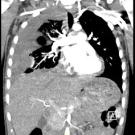

A 56-year-old woman presented to the pulmonary clinic after hospital discharge for a severe exacerbation of chronic obstructive pulmonary disease. In the last 12 months, she has presented to the hospital...

07/21/2025